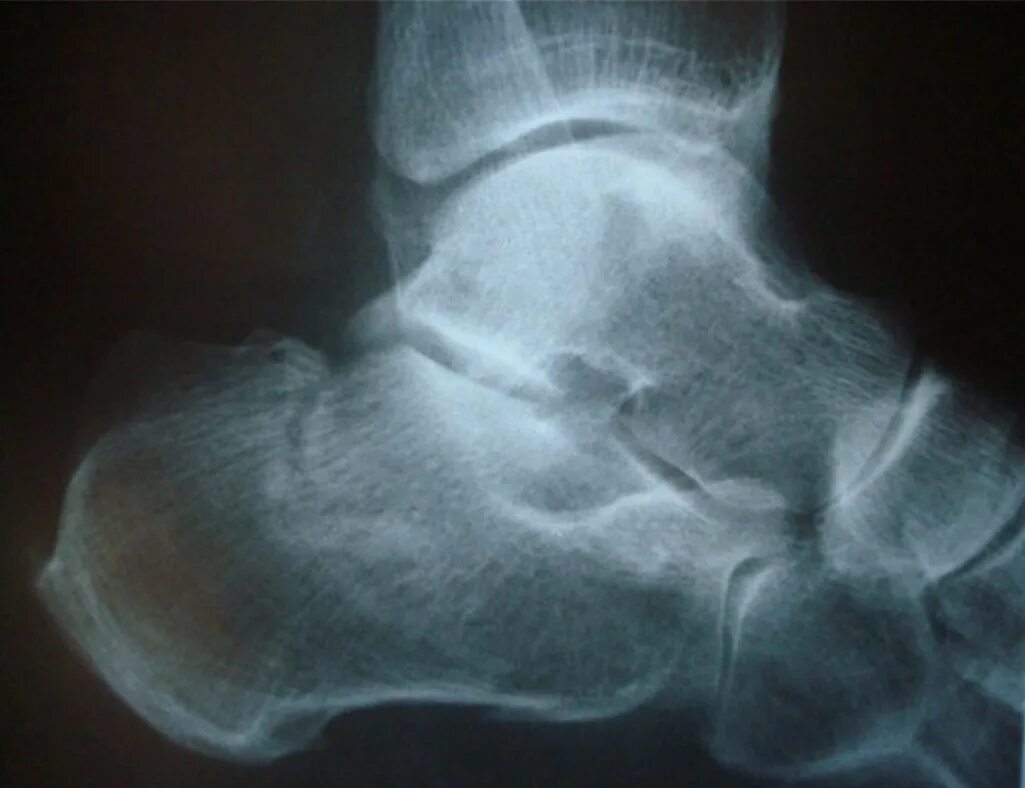

Пяточный перелом без смещения